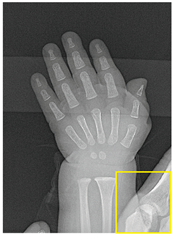

Table 2, Table 3, Table 4 and Table 5 present the results obtained through the multi-objective optimization image enhancement approach. Specifically, Table 2 and Table 3 show the results for natural images, while Table 4 and Table 5 display medical images. The tables are organized as follows: the first and second columns list the image names and their corresponding original, unenhanced versions. The third to fifth columns showcase the selected points from the Pareto front, representing the maximum contrast, knee point, and maximum detail, in that order. The final column illustrates the obtained Pareto front through the optimization process, with red, green, and orange points indicating the images that achieved maximum contrast, knee point, and maximum detail, respectively.

Table 4.

Medical image results—1.

Table 5.

Medical image results—2.

As observed in the results, the images extracted from the Pareto front significantly maximize contrast and detail compared to the original images. In all study cases, the original image is dominated by the solutions extracted from the fronts, demonstrating the approach’s effectiveness in improving visual quality. However, the differences among the three enhanced images for each problem require a more detailed analysis.

For medical images, there are instances where differences are more perceptible. For example, in the Medical3 image, the maximum contrast solution makes it difficult to visualize the internal details of the basophil (a white blood cell highlighted in the box), which could result in a less accurate interpretation. In contrast, the knee and maximum detail solutions provide a clearer view of the interior of the white blood cell. Similarly, in the Medical5 image, the maximum contrast solution highlights the hand and arm bone structures. However, the maximum detail image offers a more precise view of the internal structures within the bones (see the highlighted region), which is crucial for a more detailed evaluation. Another notable example is the Medical8 image, where the maximum detail solution offers a more detailed view of the internal structure of the eosinophil (another type of white blood cell). However, the maximum contrast image improves the visibility of red blood cells. As shown in the yellow box, this solution reveals a red blood cell that is nearly imperceptible in the other solutions. An interesting case is the Medical6 image, where only a few non-dominated solutions are present on the Pareto front. Despite the similarities among the preferred solutions, the nodules are much more perceptible in the enhanced images than in the original image, as observed in the highlighted region.